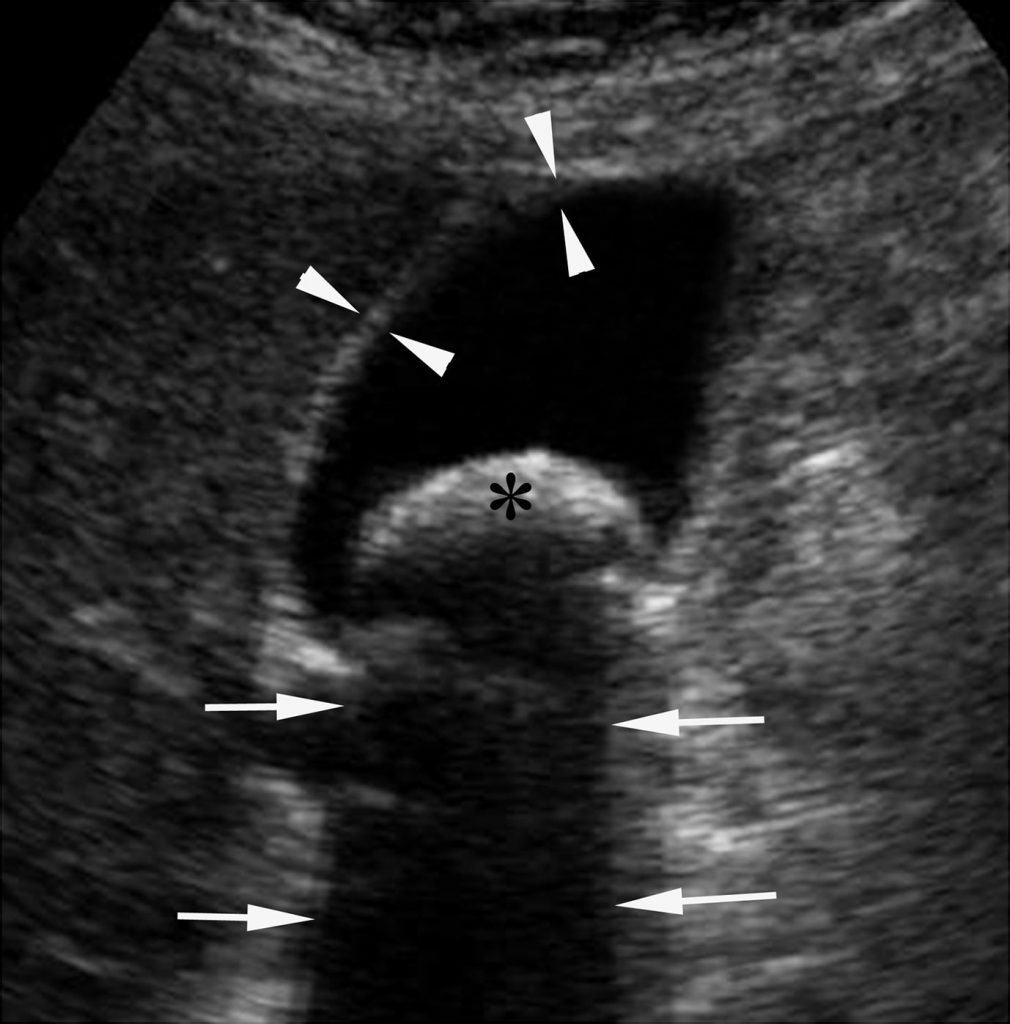

Fig. 9.4 Aspect échographique d’une cholécystite aiguë.

La vésicule biliaire (flèches) présente des parois épaissies mesurées à 9 mm d’épaisseur (entre les têtes de flèches). L’aspect de la paroi apparaît par endroits feuilleté ou strié (tête de flèche creuse). Par ailleurs, la vésicule biliaire contient du sludge déclive (∗). Il n’y a pas de calcul vésiculaire visible sur l’image.

Outre la mise en évidence des calculs vésiculaires, un épaississement de la paroi vésiculaire (> 4 mm) et une distension vésiculaire doivent être recherchés. Ce sont les images clés du diagnostic.

Les autres signes à rechercher sont importants pour consolider le diagnostic mais peuvent manquer ; ce sont :

- un signe de Murphy échographique : douleur au passage de la sonde sur la vésicule ;

- des anomalies du contenu vésiculaire : le sludge, qui correspond à une bile épaisse contenant des débris échogènes qui apparaît plus ou moins abondante et déclive dans la lumière vésiculaire ;

- un épanchement périvésiculaire.